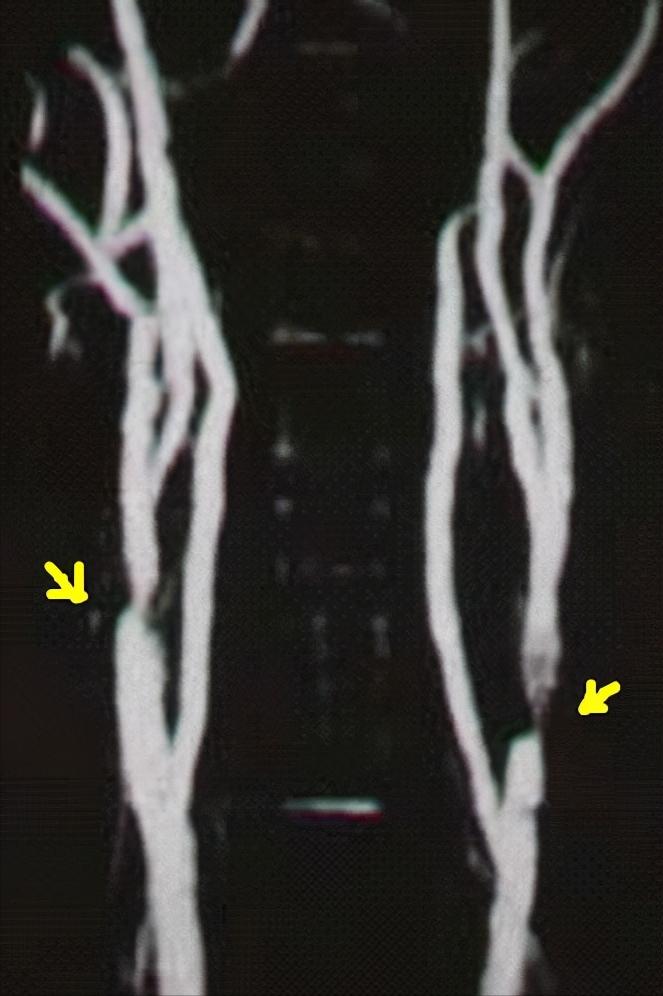

颈动脉磁共振血管造影 , 右侧颈内动脉起始部明显狭窄达90%;左侧颈动脉分叉处明显变细,波及颈内动脉,狭窄程度达95% ,双侧血管管壁形态不规则,局部硬化斑块形成。

至此,诊断明确, 双侧颈动脉重度狭窄致脑梗死、短暂性脑缺血发作 。